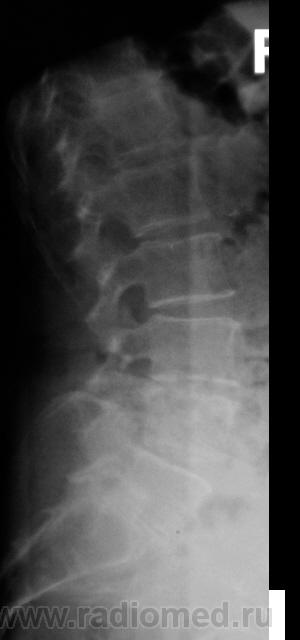

1. пациентка

2. форма позвонка - односторонне-вогнутая

3. контуры "вдавления" верхней замыкательной пластинки относительно четкие

4. елементы слероза по контуру "вдавления"

Пациентке 65 лет. Клиника радикулита.

тоже увиделись такие же характеристики зоны интереса, да и м\п диск снижен в этом сегменте + диф. остеопороз = может это такая грыжа диска?

В первую очередь думаю о негативных последствиях постменопаузального остеопороза (такая форма позвонков при патологической их компрессии вполне возможна).

4 - на Т-грамме не понравились замыкат. пластинки (больше краниальная) И L6 (И смежные L2, L3 - в последних, возможно, грыжевые вдавления)...

Сколиоз, остеохондроз, большая красивая центральная грыжа Шморля и сужение межпозвонковых отверстий. Вполне достаточно для клиники радикулита.

Направление было на рентгенографию поясничного отдела с целью исключить деструкцию и подтвердить дегенеративные изменения. Валентин Львович, по-моему, приведённые исследования достаточно полные для заключения.